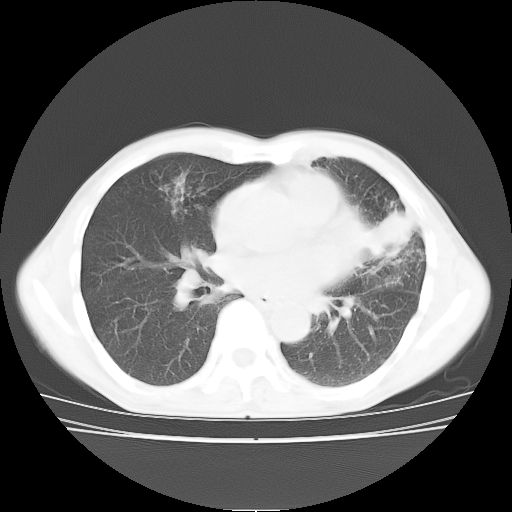

标题: CT25795:感冒后反复咳嗽两月余,痰中带血半月余。X诊断“肺 [打印本页]

标题: CT25795:感冒后反复咳嗽两月余,痰中带血半月余。X诊断“肺

1.双肺肺梗塞(理由:病灶呈三角形,与胸膜相连且局部胸膜肥厚,左心室增大)伴肺感染。

2.一元论双肺感染。

肺梗塞虽然有创意,但不现实。我考虑感染性病灶。

考虑两肺感染性病变,左肺上叶舌段肿瘤性病变待排;建议抗炎治疗后复查。